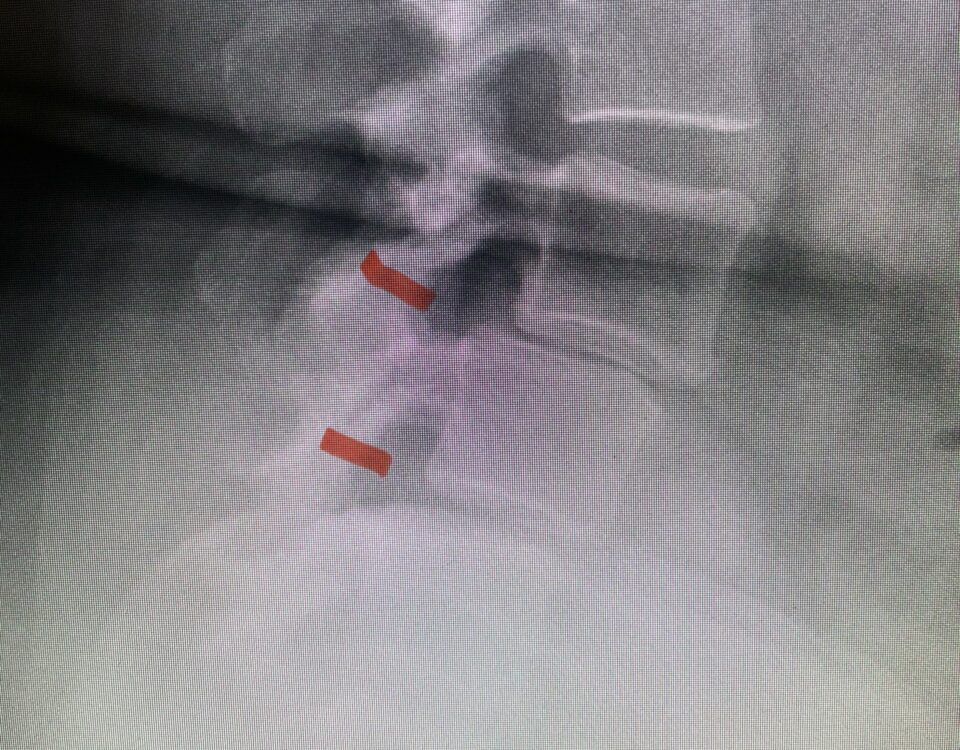

The actual structural cause of lumbar thecal sac compression can vary in degenerative spondylolisthesis and stenosis. The culprits are commonly thickened ligamentum flavum or severe facet […]